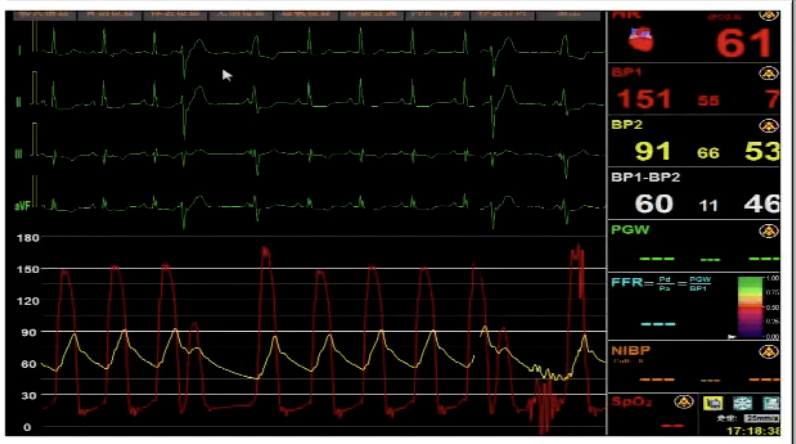

导管测压,压力阶差60mmHg:

释放中期,快速起搏下释放到80%切换视图,并借助食管心超评估深度和反流情况:

术后导管测压压差为2mmHg: